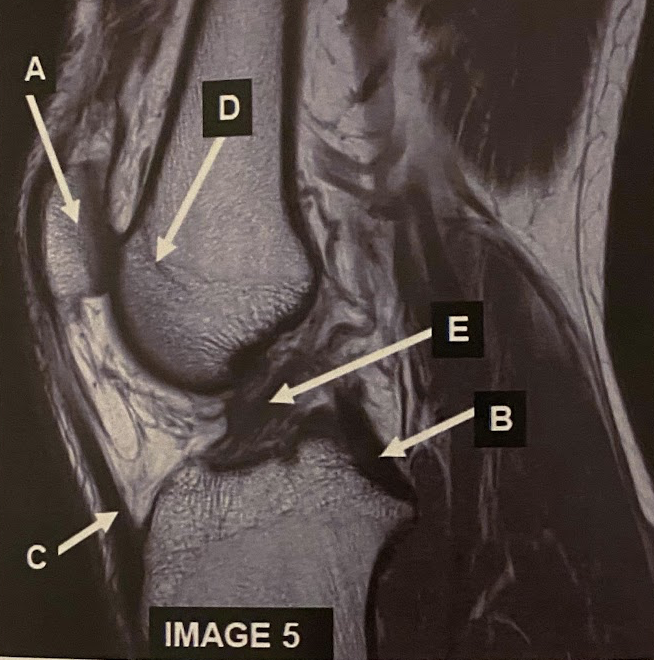

What anatomy does letter A demonstrate?

A

Patella

Q

What anatomy does letter B demonstrate?

PCL

22

What anatomy does letter C demonstrate?

Patellar Tendon

23

What anatomy does letter D demonstrate?

Femoral Condyle

24

What anatomy does letter E demonstrate?

ACL